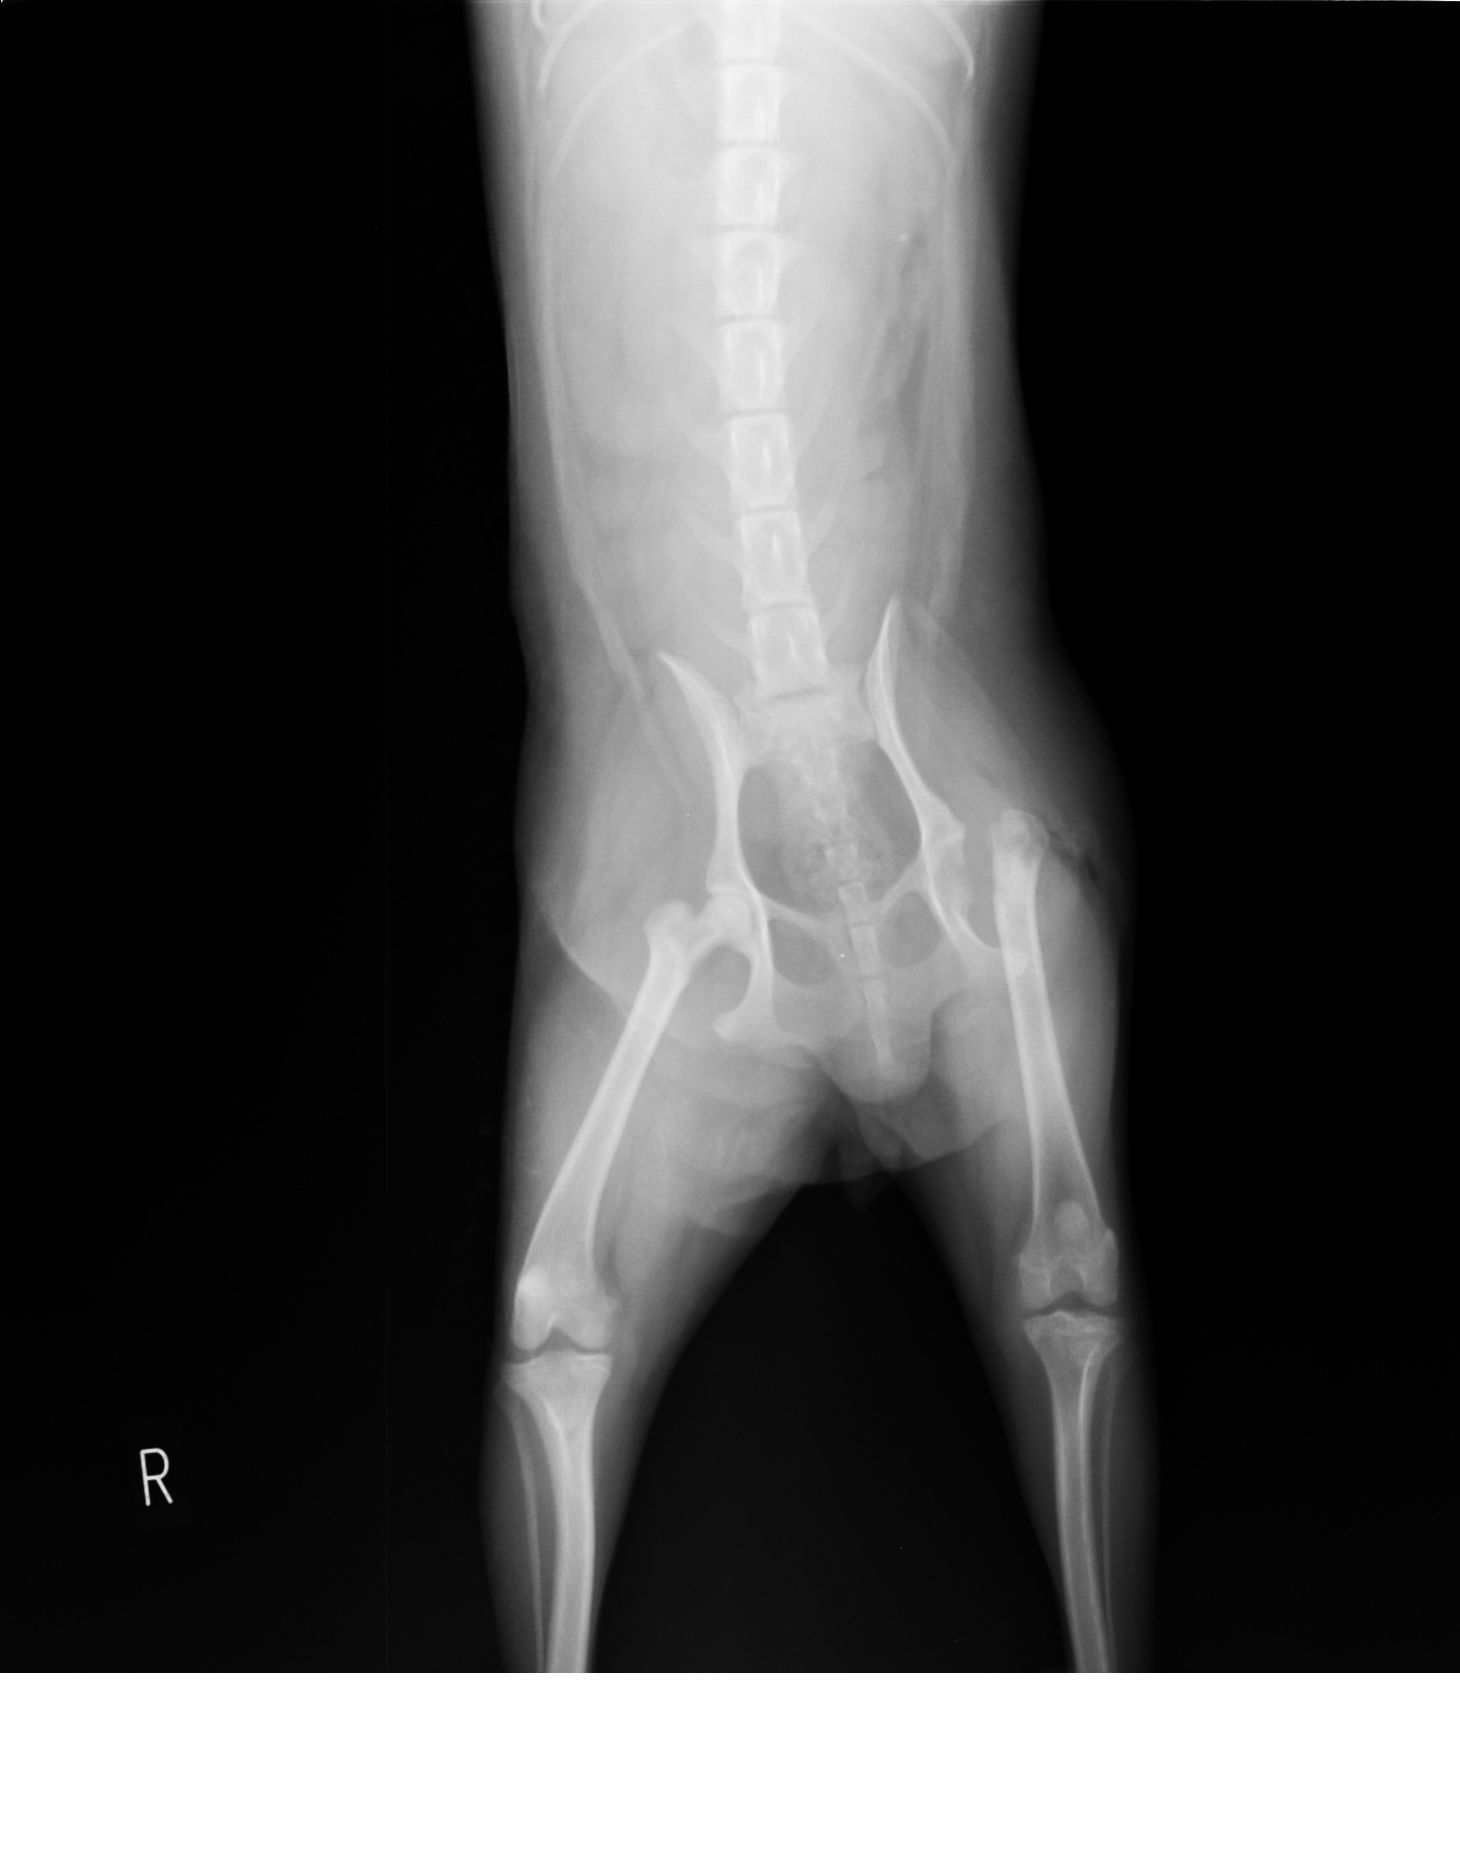

別の猫の症例